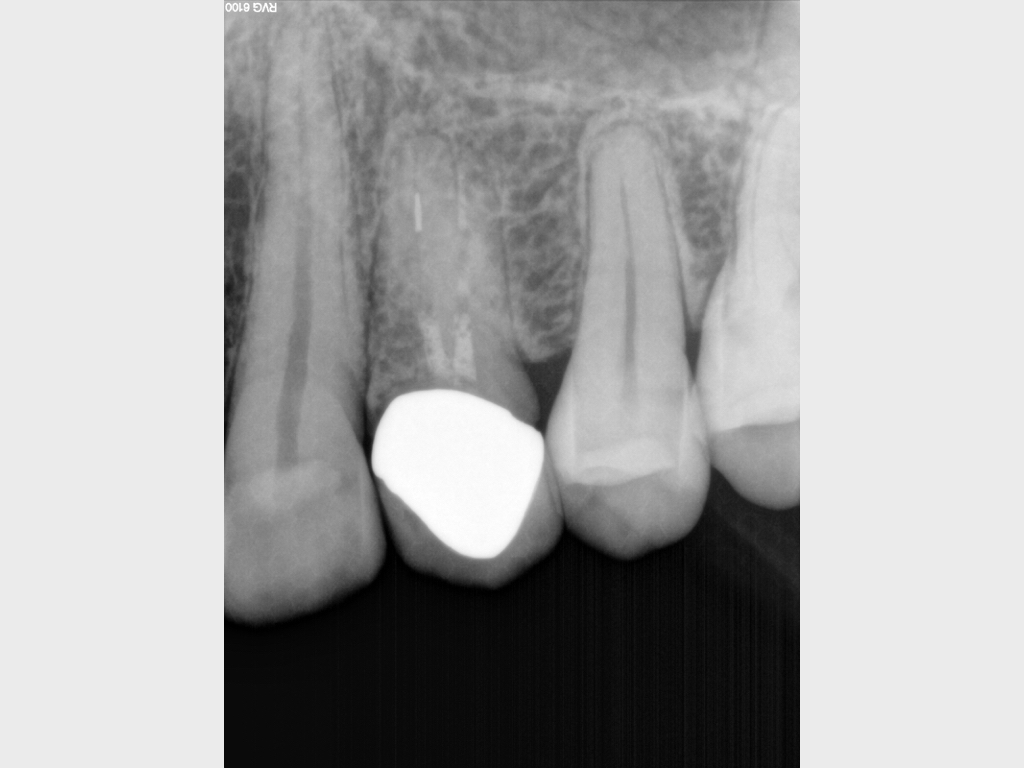

7078.001

Routine